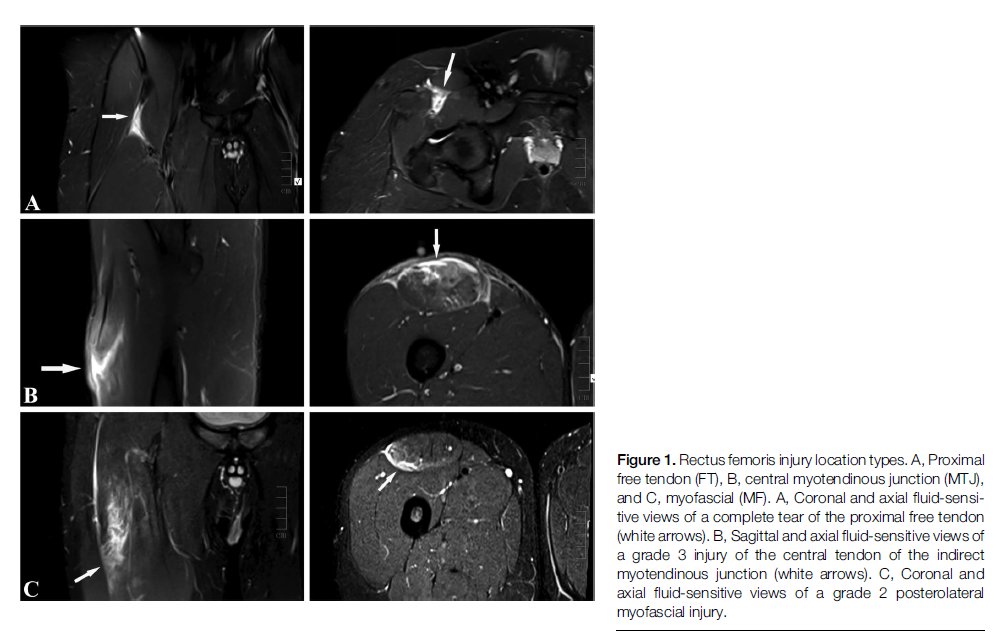

Rectus femoris-the neglected step-child of thigh muscle injury in football finally getting some love with the largest MRI documented series to date Free tendon injuries only associated with kicking (not sprints) Rehab & injury prevention implications dx.doi.org/10.1097/JSM.00…

Rectus femoris-the neglected step-child of thigh muscle injury in football finally getting some love with the largest MRI documented series to date

Free tendon injuries only associated with kicking (not sprints)

Rehab & injury prevention implications